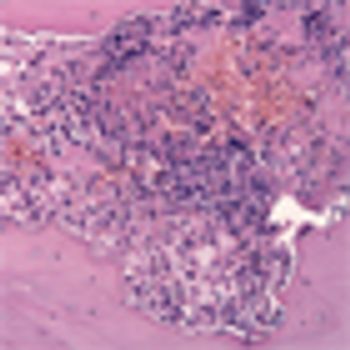

This slide show features images of diffuse osteoblastic bone metastases in a 70-year-old advanced prostate cancer patient, bone metastases in the vertebral column of a kidney cancer patient, and more.